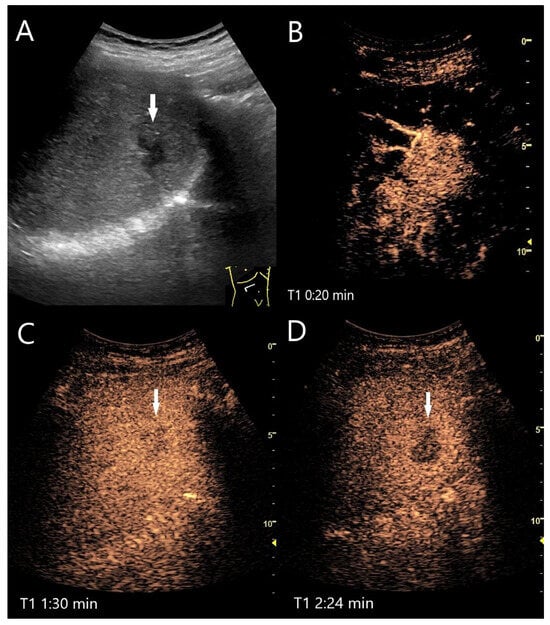

Figure 4.

FNH. Incidental finding as part of the diagnosis of choledocholithiasis. 20 mm large, slightly hypoechoic lesion (arrow) with contour protrusion of the liver, centrally visible vessel on color Doppler imaging (CDI) (A). In the CEUS, wheel-spoke-like central enhancement (B) and homogeneous hyperenhancement in the AP (C) is seen. In the PVP after 60 s, a very shallow washout begins (D). This continues in the LP at 2:05 min (E) and is very pronounced after 3:25 min (F). This was the reason for a US-guided biopsy. The histology was consistent with FNH with focal fibrosis.